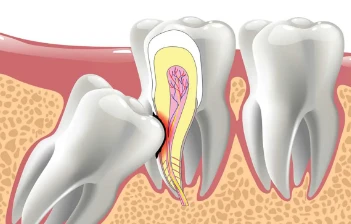

You may require a root canal if your teeth are extremely sensitive or painful. Al Khaja Medical Centre provides excellent root canal treatments in Abu

There may be more than simply a cavity if you have ongoing tooth discomfort, swelling, or trouble opening your mouth. These may indicate that you requ